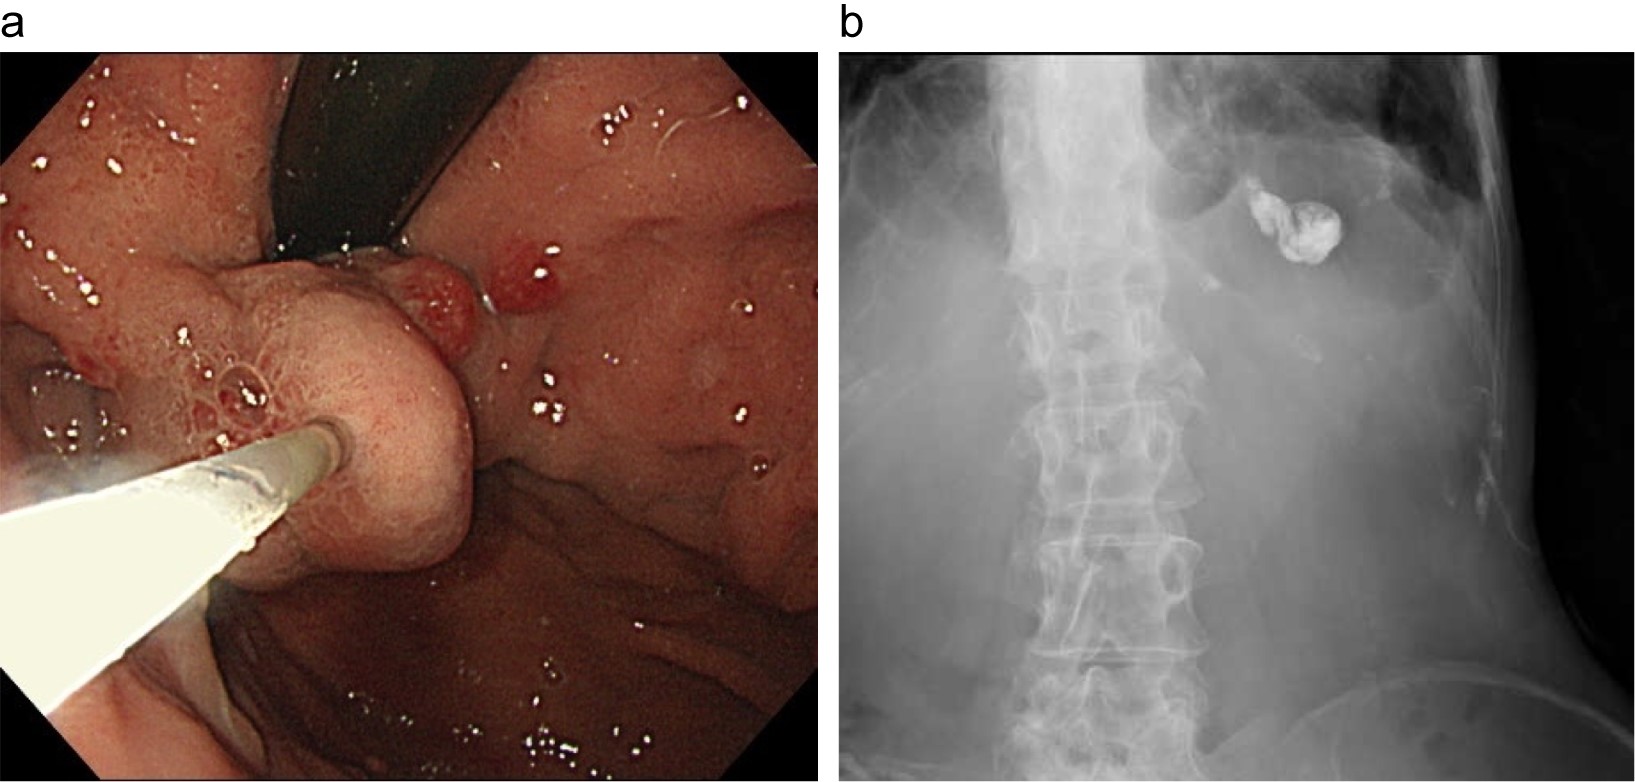

Histoacrylを用いた内視鏡的塞栓療法

a: 内視鏡的塞栓療法の内視鏡像。胃穹窿部の静脈瘤を穿刺し、Lipiodol添加 Histoacrylを注入している。

b: 内視鏡的塞栓療法後のエックス線写真。左上腹部にLipiodol添加 Histoacrylが停滞している。